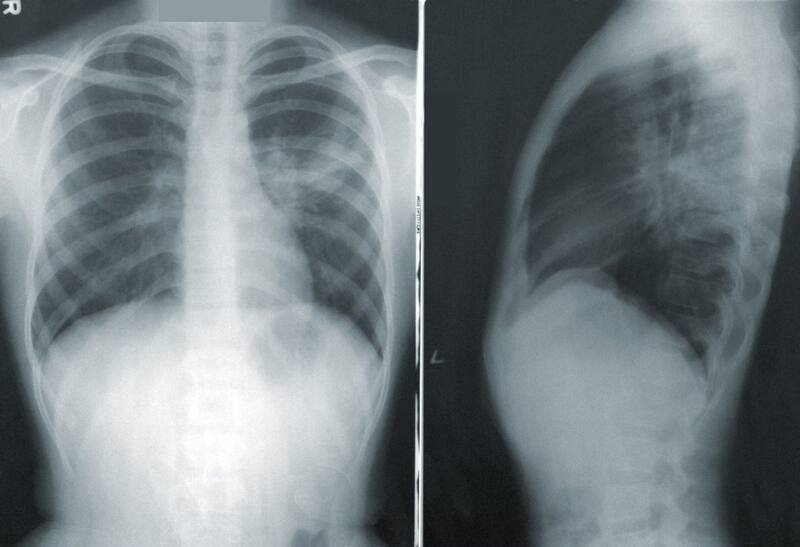

El papa Francisco presenta una neumonía bilateral y una infección polimicrobiana del tracto respiratorio, que significa que está infectado por virus y bacterias.

La neumonía bilateral diagnosticada al papa Francisco es una infección respiratoria que, en este caso, afecta a los dos pulmones.

Según explica Mayo Clinic, esta enfermedad provoca la inflamación de los sacos de aire de los pulmones y pueden llenarse de líquido o pus. Los síntomas suelen ser tos con flema o pus, fiebre, escalofríos y dificultades para respirar.

“La tomografía computarizada de tórax a la que se sometió esta tarde el Santo Padre, prescrita por el equipo sanitario vaticano y por el equipo médico de la Fundación Policlínico ‘A. Gemelli’, demostró la aparición de neumonía bilateral que requiere terapia farmacológica adicional”, se lee en el informe.